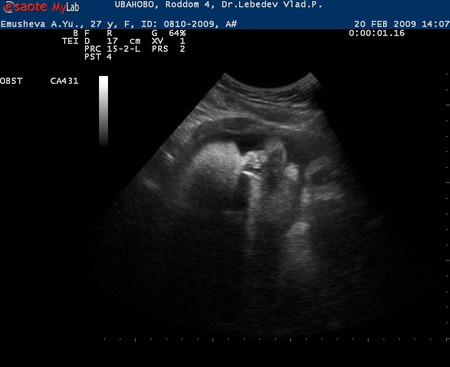

Это наше узи ровно в 33 недели! Остальные фотки в альбоме.

Сегодня нам ровно 33 недели!